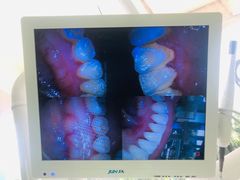

• 众鑫医疗小白牙口腔(土桥店)

• -众鑫医疗小白牙口腔(土桥店)

娜妹子 | 20-07-29